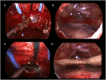

Objective: Rathke's cleft cysts (RCCs) are quite uncommon sellar lesions that can extend or even arise in the suprasellar area. The purpose of this study is to evaluate the effectiveness of both standard and extended endoscopic endonasal approaches in the management of different located RCCs.

Results: A standard transsphenoidal approach was used in 19 cases, while the extended variation of the approach in 10 cases (5 purely suprasellar and 5 intra-suprasellar RCC). Cysts contents was fully drained in all the 29 cases, whilst a gross total removal, that accounts on the complete cyst wall removal, was achieved in an overall 55,1% of patients (16/29), specifically 36,8% (7/19) that received standard approach and 90% (9/10) of those that underwent to extended approach. We reported a 56.2% of recovery from headache, 38.5% of complete recovery and 53.8% of improvement from visual field defect and an overall 46.7% of improvement of the endocrine functions. Postoperative permanent DI rate was 10.3%, overall post-operative CSF leak rate 6.9%; recurrence/regrowth occurred in 4 patients (4/29, 13.8%), but only one required a second surgery.

Conclusion: The endoscopic transsphenoidal approach for the removal of a symptomatic RCC offers several advantages in terms of visualization of the surgical field during both the exposure and removal of the lesion. The "extended" variation of the endoscopic approach provides a direct access to the supradiaphragmatic space, allowing adequate view and room for the safe removal of selected supradiaphragmatic RCCs, regardless of the sellar size (even a not enlarged sella), and provides a higher likelihood of preserving normal pituitary tissue and functions.